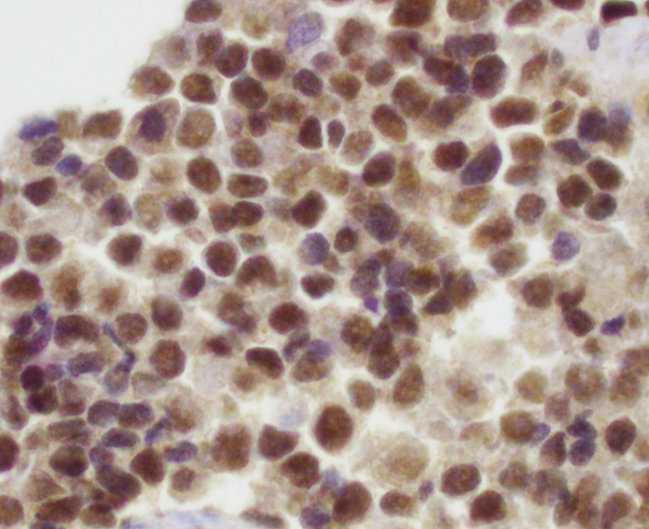

Microscopic (histologic) images

- NKX2.2 (high specificity) (Am J Surg Pathol 2012;36:993)

- FLI1 (nuclear staining with EWSR1-FLI1 fusion, ~90%) (Am J Surg Pathol 2000;24:1657, Appl Immunohistochem Mol Morphol 2001;9:255)

- ERG (nuclear staining with EWSR1-ERG fusion) (Mod Pathol 2012;25:1378)